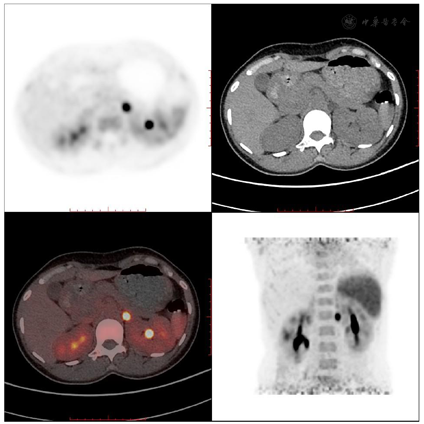

入院后血压151/96 mmHg。完善相关辅助检查提示:电解质5项:K 1.80 mmol/L(参考范围:3.5~5.3 mmol/L),Na 148.9 mmol/L(参考范围:137~147 mmol/L)。头颅、颈部CT平扫:左枕顶部皮下软组织肿胀并少许血肿;泛发型副鼻窦炎。腹部增强CT:左侧肾上腺结节,考虑腺瘤;双肾多发小结石。高血压4项:COR 8:00 19.37 μg/dl(参考范围:6.40~21.00 μg/dl),ACTH 8:00 11.14 pg/ml(参考范围:6.00~48.00 pg/dl),ALD 19.30 ng/dl(参考范围:立位0.00~35.30 ng/dl),REN <0.50 μIU/ml(参考范围:立位4.40~46.10 μIU/ml)。卡托普利试验前:ALD 24.10 ng/dl,REN <0.50 μIU/ml。卡托普利试验后:ALD 25.00 ng/dl,REN 0.71 μIU/ml。盐水负荷试验前:ALD 38.80 ng/dl;REN <0.50 μIU/ml;盐水负荷试验后:ALD 24.50 ng/dl,REN <0.50 μIU/ml。68Ga-Pentixafor PET/CT(图1)提示:1、左侧肾上腺体部结节伴CXCR4(CXC chemokine receptor type 4)高表达,考虑醛固酮腺瘤(Aldosterone-Producing Adrenal Adenomas,APA)可能。2、双肾多发小结石。

本例年轻患者临床表现为高血压、低血钾,不难想到原发性醛固酮增多症的可能,通过完善相关实验室检查确诊了原发性醛固酮增多症。患者的腹部CT提示了左侧肾上腺腺瘤,但是仅依据CT或MRI检查,并不能确定患者的原发性醛固酮增多症是否是由该腺瘤分泌过多醛固酮所致。为了进一步明确患者是否为醛固酮腺瘤,患者接受了68Ga-Pentixafor PET/CT显像,显像结果显示左侧肾上腺结节CXCR4高表达,提示为分泌醛固酮的功能性组织,从而得出醛固酮腺瘤的诊断。68Ga-Pentixafor PET/CT显像是一种高度敏感和特异且无创性的APA定位诊断方法。